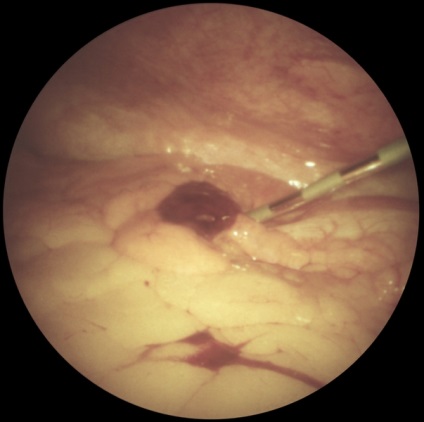

Az első lépés a bevezetése pneumoperitoneum L. a. A hasat kilyukadt egy speciális tű (a tű típusától Leriche) a bal alsó pont nyomkövetés (ábra. 1). A hasüreget adjuk 3000-4000 cm3 levegőt. dinitrogén-oxid vagy szén-monoxid. Attól függően, hogy a célkitűzések a tanulmány beadásra laparoszkópon egyik kiválasztott pontok szerinti rendszer felkutatása gyakran fent és bal oldalán a köldök. Szike, hogy egy bőr bemetszést 1 cm. Boncolással a bőr alatti szövet, és a fascia a rectus abdominis. Ezután, a hüvely trokár szúrja a hasfal, a trokár eltávolítják, és ezen keresztül a hüvely kerülnek bevezetésre laparoszkópot. Ellenőrzés a has szakaszosan végezzük jobbról balra, megtekintésekor a jobb oldali csatorna, a máj, obstruktív és mellékvese térben szubdiafragmatikus helyet. bal oldalsó csatornát medencét. Meg lehet változtatni a helyzetét a beteg részletesebb ellenőrzést. A színe, jellege a felület, az alak a test átfedések, hiszen folyadékgyülem lehet beállítani lézió jellege: májzsugor (2A ábra.) Metasztatikus (2b ábra.), Heveny gyulladás (2. ábra, d.) nekrotikus folyamat (ábra. 2, stb), stb A diagnózis megerősítésére biopszia (általában egy defekt). Széles körben használják különböző orvosi eljárásokban L. hasi vízelvezető (3A.), Mikroholetsistostomiya (ábra. 3b), és mások. Lezárását követően laparoskipii laparoskona és extrahálás a hasüregből a gáz eltávolítása után a bőrön sebet lezárjuk 1- 2 öltés.

Ábra. 3b). Kombinált laparoszkópia orvosi manipulációk - mikroholetsistostomiya.

Ábra. 3a). Kombinált terápiás manipulációk laparoszkópia - hasi vízelvezetés pancreonecrosis.